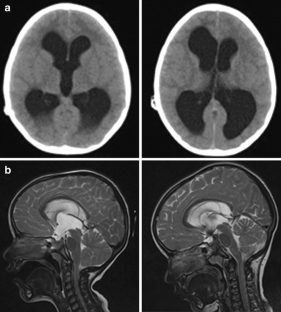

Fig. 2